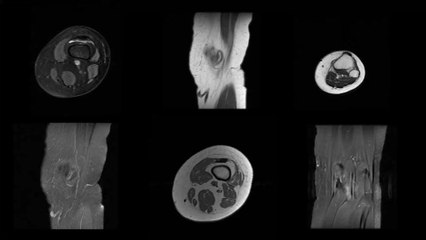

Appendice : définition, côté, rôle, douleur, de quoi s'agit-il ?